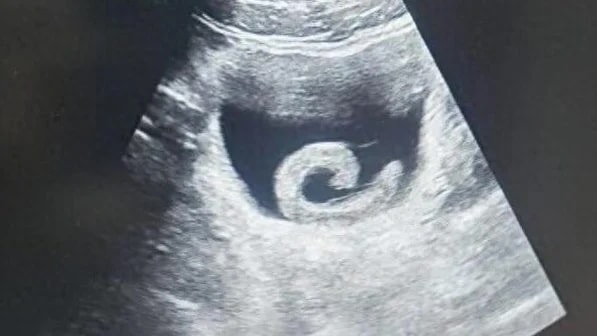

Con đỉa đã gây ra cho Zheng những cơn đau dữ dội đến mức anh không còn lựa chọn nào khác ngoài việc đến phòng cấp cứu của một bệnh viện địa phương. Khi nghe lý do, các bác sĩ không khỏi sửng sốt. Kết quả siêu âm xác nhận đúng như anh trình bày: một con đỉa sống đang ở trong bàng quang. Ngay lập tức, các bác sĩ chuẩn bị cho ca phẫu thuật khẩn cấp nhằm loại bỏ ký sinh trùng và cứu mạng bệnh nhân.